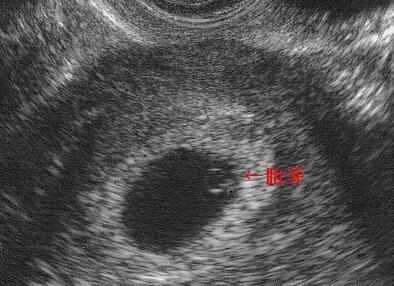

1、胎囊(GS)

胎囊也叫孕囊,胎囊只在怀孕早期见到。月经28~30天规则来潮的妇女,停经35天,B超就可以在宫腔内看到胎囊。

胎囊的位置:胎囊位置在子宫的宫底、前壁、后壁、上部、中部都属正常;形态圆形、椭圆形、清晰为正常;如胎囊为不规则形、模糊,且位置在下部,孕妇同时有腹痛或阴道流血时,可能要流产。

胎囊的大小:怀孕6周时胎囊直径约2厘米,孕10周时约5厘米,孕1.5个月时直径约2厘米,2.5个月时约5厘米为正常。